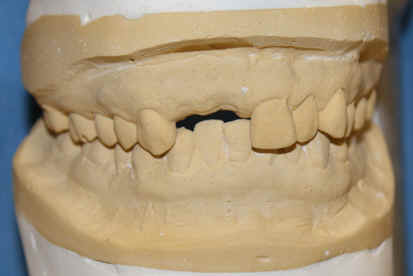

A 43 year-old lady has lost #7 and 8 due to caries for ~ 2 year. It appears that the ridge is wide (Fig.1). To place implants in ideal position, cone beam CT is planned. Models are mounted (Fig.2); diagnostic wax-up is finished (Fig.3). Drill sleeves (arrowheads in Fig.4; 10 mm long, 2.2 mm in diameter; Straumann) are placed lingual to the incisal (I) edges of the neighboring teeth. The position of drill sleeves is confirmed by CT: between the incisal edge and the cingulum (Fig.5). The cross sections at #7, 8 and 9 are shown in Fig. 6, 7 and 8, respectively. However, the long axis of the sleeve (S) or the natural tooth #9 is not aligned with that of the alveolar ridge. This orientation is good from prosthetic viewpoint, but we cannot place a long or wide implant. The lateral view of the three-dimensional image shows that the long axis of the crown (C) of #9 is not in line with that of its root/ridge (R, Fig.9). It appears that the trajectory of an implant should be not decided by wax-up, but should be adjusted to accommodate the morphology of the alveolar ridge. In all, the drill sleeve (S) should be moved and tilted more labially to place the longest and largest implant.